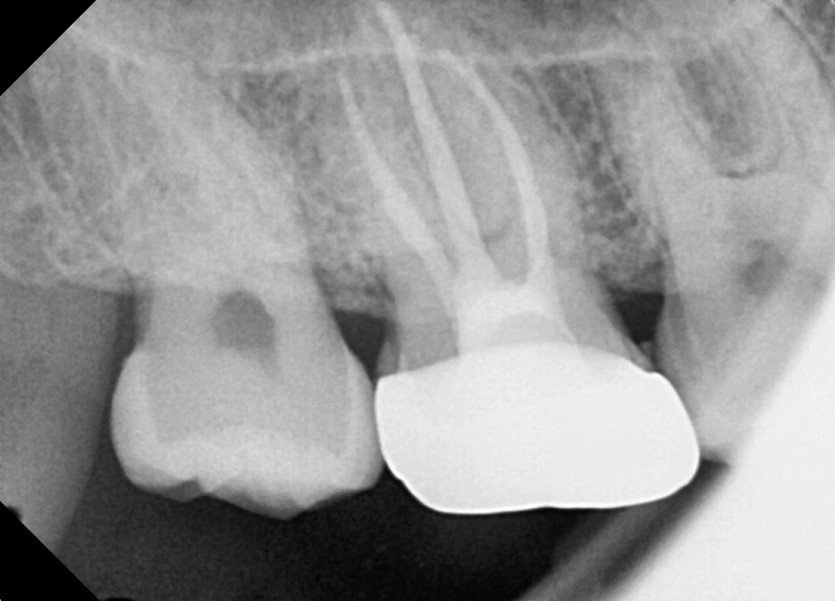

#18,48 사랑니 발치

구강 외과 전문의가 당일 발치했습니다.